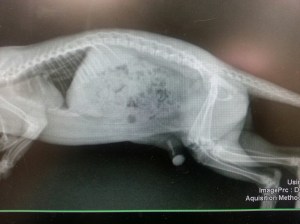

We took x-rays of her pelvis and legs as well as her chest and abdomen to look for other injuries.

The x-ray confirmed a complete femoral fracture as well as multiple hip fractures and SI luxation. I contacted several veterinarians to ask about orthopedic repair. Unfortunately, the lowest estimate we got was $2000. This is a significant amount of money for a non-profit organization and not something we can do. So I decided to do my best and fix the fracture.

I have repaired a grand total of ONE fracture in my 18 year career (I usually send them to a specialist). so you can imagine that I was a bit stressed and fairly anxious for this procedure. As it turns out, I was able to get the bones realigned and stabilized the fragments with a pin. I can’t explain the immense relief I felt when I saw this x-ray of the pin seated just right!